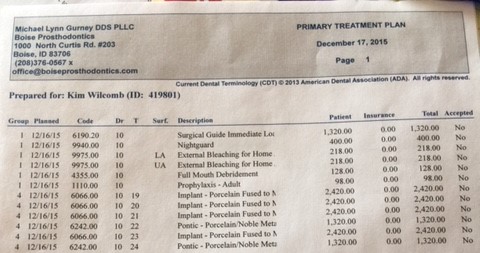

In anticipation of the second tumor, Kim is still needing to address the reconstruction of the removal of the original tumor. At this stage, one-year post surgery, the plan is to begin the preparation for porcelain implants, or a new set of teeth. In order to do this, Kim will face a third surgery in which five metal posts will be implanted into the graphed bone in her jaw. This surgery cost is roughly $9,795. However, the quote only includes 30 minutes of general anesthesia, and the doctors anticipate surgery could take up to an hour and a half.

Following the third surgery, if all goes as planned, it should take about 4-6 months of tissue recovery before Kim faces another surgery in which the surgeon will re-expose the five metal posts and cap them in order to prevent further tissue growth. Once the posts are capped, Kim will face another 4-6 months of healing. This fourth surgery has yet to be quoted, but given previous experiences it is only fair to assume that it will be costly.

Once these two surgeries regarding the metal posts have occurred and recovery is successful, Kim will finally be given a new set of teeth on the left side. (Remember, this is without any knowledge of that second tumor of the right or the cost that will come with it). Although this seems far off in time at this point, the initial cost covers all surgeries and stages of the process regarding the porcelain implants. The current quote for the teeth and jaw replacement is $19,542.

In anticipation of the second tumor, Kim is still needing to address the reconstruction of the removal of the original tumor. At this stage, one-year post surgery, the plan is to begin the preparation for porcelain implants, or a new set of teeth. In order to do this, Kim will face a third surgery in which five metal posts will be implanted into the graphed bone in her jaw. This surgery cost is roughly $9,795. However, the quote only includes 30 minutes of general anesthesia, and the doctors anticipate surgery could take up to an hour and a half.

Following the third surgery, if all goes as planned, it should take about 4-6 months of tissue recovery before Kim faces another surgery in which the surgeon will re-expose the five metal posts and cap them in order to prevent further tissue growth. Once the posts are capped, Kim will face another 4-6 months of healing. This fourth surgery has yet to be quoted, but given previous experiences it is only fair to assume that it will be costly.

Once these two surgeries regarding the metal posts have occurred and recovery is successful, Kim will finally be given a new set of teeth on the left side. (Remember, this is without any knowledge of that second tumor of the right or the cost that will come with it). Although this seems far off in time at this point, the initial cost covers all surgeries and stages of the process regarding the porcelain implants. The current quote for the teeth and jaw replacement is $19,542.